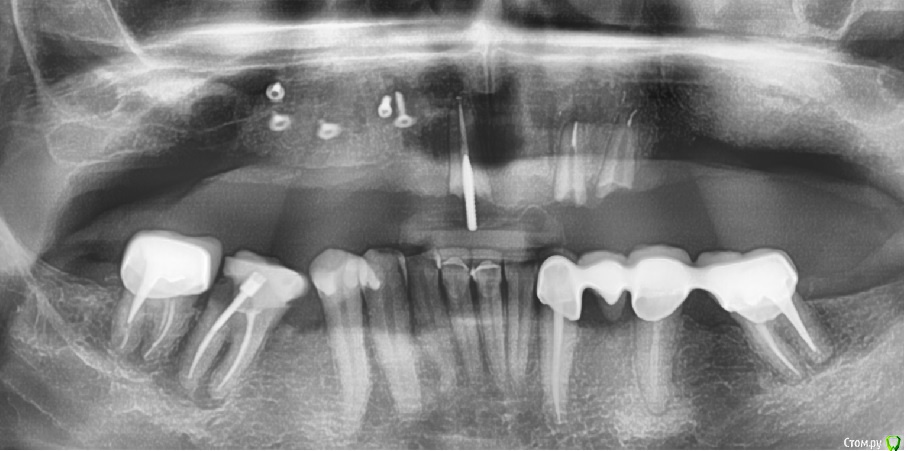

kamranchick Опубликовано 15 сентября, 2018 Поделиться Опубликовано 15 сентября, 2018 Господа чтобы не плодить темы, надеюсь суворовец не против)НКР вместе с синусом было 2 недели назад, через неделю на осмотре был большой отек и расхождение швов по центру, пациент честно сказал что нижние зубы били именно в центр.на сегодняшний день картина вот такая, какие будут рекомендации?Ванночки и ждем, либо? P.S ничего не болит у пациента, пациент приятный честный.НКР вел под амоксиклавом, нимесилом и хг.Эволюшн мембрана, биосс С и ауто немного...фоткал на телефон, фотоаппарат временно на реконструции)От соседнего зуба инфекция мало вероятна, разрез до него не доводил. Ссылка на комментарий

zubovolok Опубликовано 4 октября, 2018 Поделиться Опубликовано 4 октября, 2018 Господа чтобы не плодить темы, надеюсь суворовец не против)НКР вместе с синусом было 2 недели назад, через неделю на осмотре был большой отек и расхождение швов по центру, пациент честно сказал что нижние зубы били именно в центр.на сегодняшний день картина вот такая, какие будут рекомендации?Ванночки и ждем, либо? P.S ничего не болит у пациента, пациент приятный честный.НКР вел под амоксиклавом, нимесилом и хг.Эволюшн мембрана, биосс С и ауто немного...фоткал на телефон, фотоаппарат временно на реконструции)От соседнего зуба инфекция мало вероятна, разрез до него не доводил. Коллеги планируется имплантация в позиции 1.3,1.1,2.3,2.5 пациент носит чспп верхний, без него прикус нефиксированный и фронтальные зубы нижней челюсти упираются в альвеолярный отросток, как быть после имплантации, чтобы не было такого же расхождения швов? Ссылка на комментарий